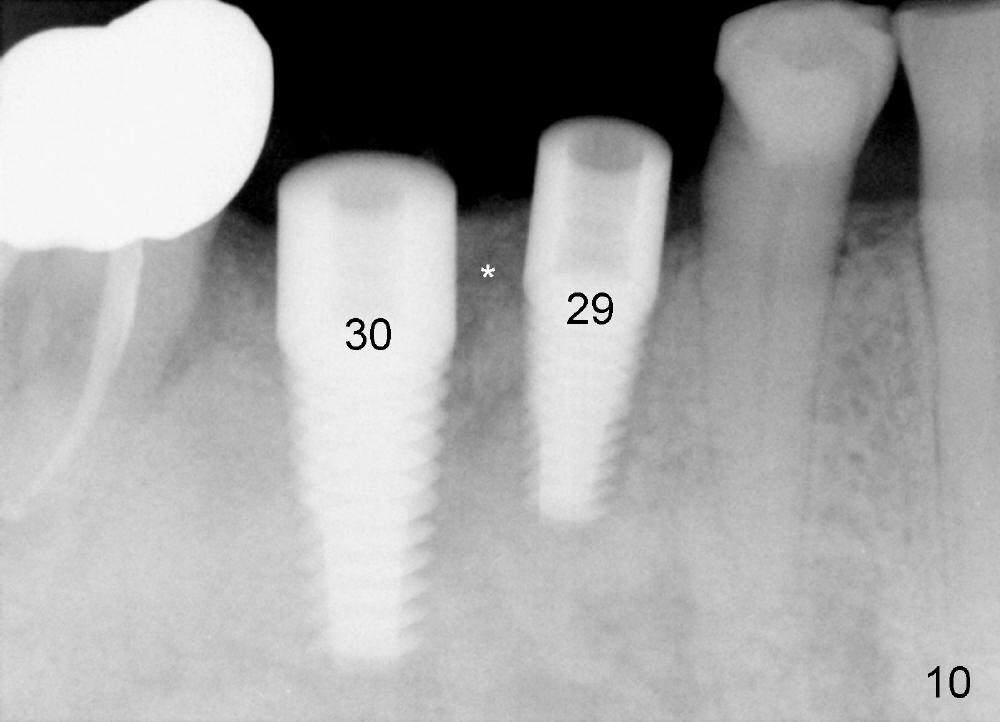

Three months later, the B-L width at the site of #29 is significantly reduced (Fig.4). Upon X-ray exam, there is decreased bone density between these two sockets (Fig.5 *). Socket preservation seems not to live its expectation. The obvious advantage is formation of callus-like bone in the molar socket (Fig.6 *, between the buccal (B) and lingual (L) plates). The significant decrease in the buccolingual width at the site of #29 is associated with buccal plate crack during implantation (Fig.7 *). At the site of #30, the lingual plate is so low that there is implant thread exposure (Fig.8 <). Mixture of autogenous bone (harvested from drilling with Bicon reamers) and synthetic bone (Osteogen) is placed mainly buccal to the implant #29 and lingual to #30 (Fig.9), followed by collagen membrane. Bone density between these two implant increases due to the bone grafting (Fig.10 *, as compared to Fig.5). In fact, the implant at the site of #29 is found loose 1 month postop.